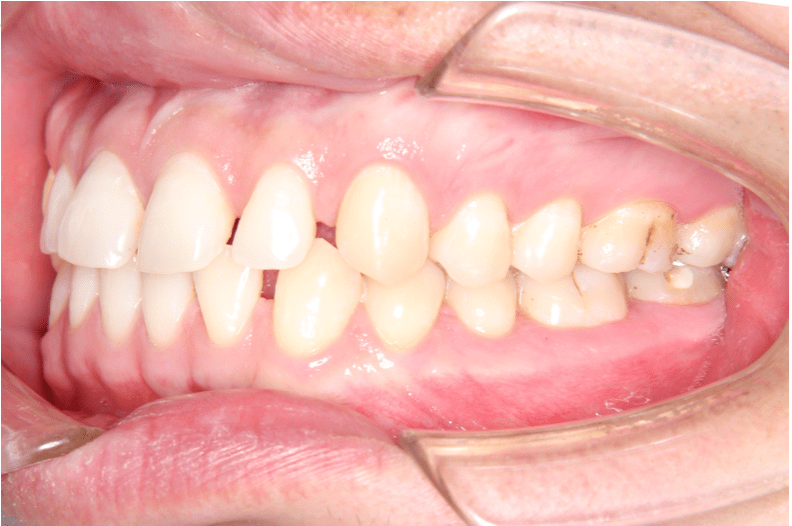

治療前(右)

歯列に隙間が見られます